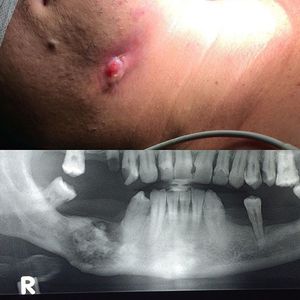

Chronic osteomyelitis on mandible

Osteomyelitis